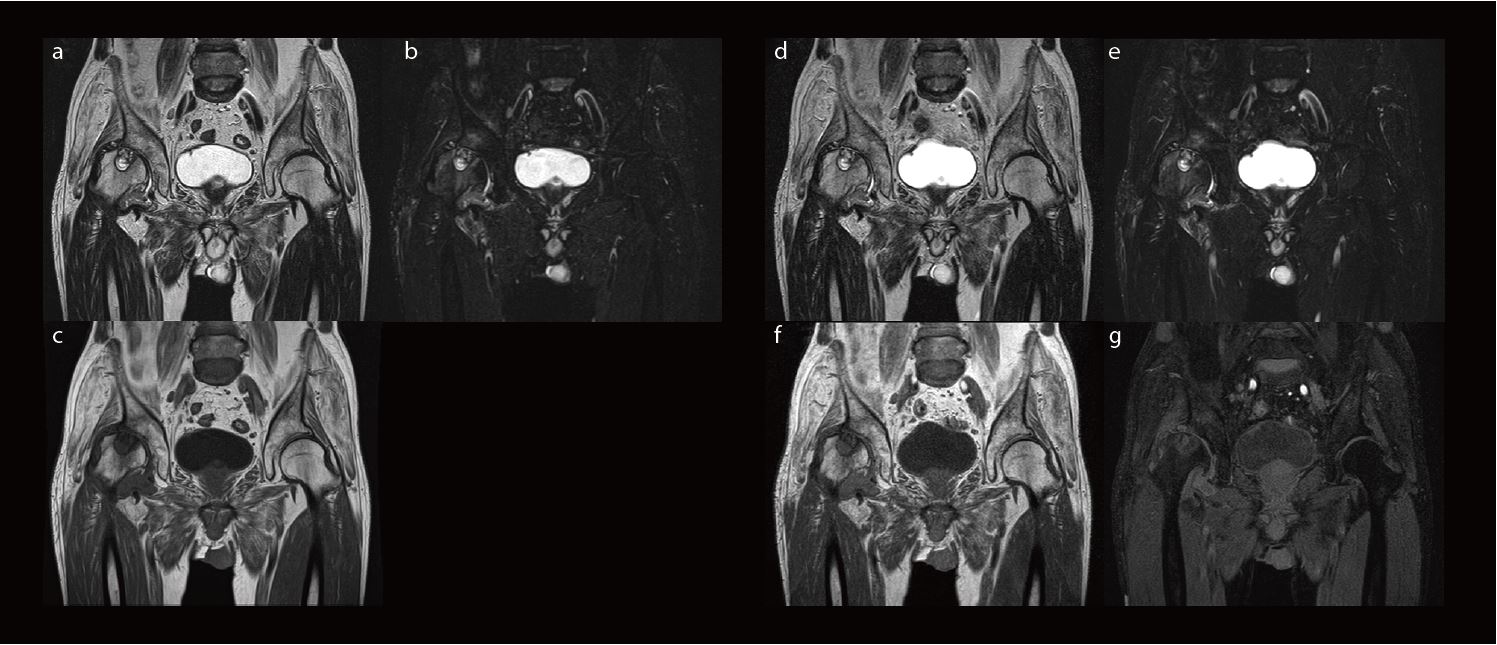

На рис. 2 наведено клінічний випадок остеоартрозу кульшового суглоба. Замість виконання трьох окремих сканувань для отримання трьох типів зображень (T2-зважених, STIR і T1-зважених зображень) було виконано два сканування за допомогою WFS DIXON для отримання чотирьох типів зображень. Чітко видно кісту правого кульшового суглобу завдяки відмінному співвідношенню сигнал/шум.

Рис.2. Ліворуч: зображення, отримані традиційним методом. (a) T2WI, (b) T2WI STIR, (c) T1WI. Праворуч: зображення, отримані за допомогою WFS DIXON. (Верхній ряд: T2WI WFS DIXON, нижній ряд: T1WI WFS DIXON) (d), (f): зображення у фазі, (e), (g): зображення води. Час сканування становив приблизно 5 хвилин для обох методів, але WFS DIXON надає чотири типи зображень, тоді як звичайний метод надає лише три типи зображень.